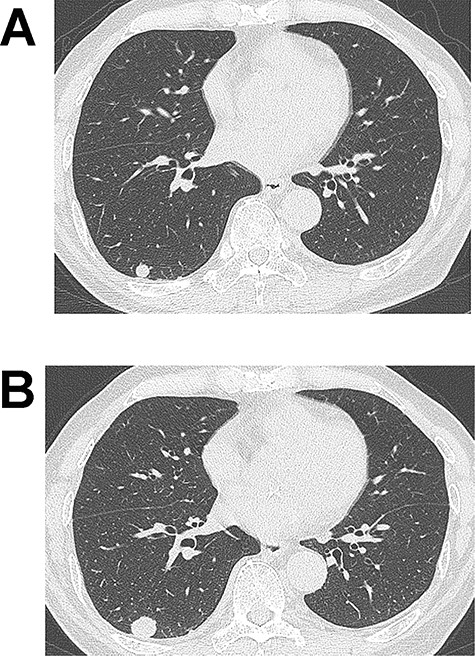

(A) Computed tomography (CT) image showing a 10-mm nodule in the lower lobe of the right lung. (B) The tumour grew to 17 mm in diameter on CT 2 years after the initial imaging.

An 83-year-old man with a 60-pack-year history of smoking was found to have an abnormal shadow on chest radiography. He was asymptomatic and laboratory test results, including tumour markers, were all normal. Chest CT revealed a 10-mm-diameter tumour in the lower lobe of the right lung (Fig. 1A). Since the tumour was well demarcated, it was suspected to be a benign lesion such as hamartoma, and the patient underwent a conservative follow-up approach. The tumour size gradually increased on CT during follow-up and subsequently reached 17 mm 2 years after the initial imaging (Fig. 1B). At that time, 18F-fluoro-deoxy-glucose positron emission tomography (FDG-PET) showed slight uptake in the right lung tumour (maximum standardized uptake: 1.71). Since malignancy could not be completely ruled out, surgery was scheduled. Wedge resection of the right lower lobe was performed using video-assisted thoracic surgery. Intraoperative frozen section diagnosis revealed a tumour with spindle cells that did not contain a malignant component.